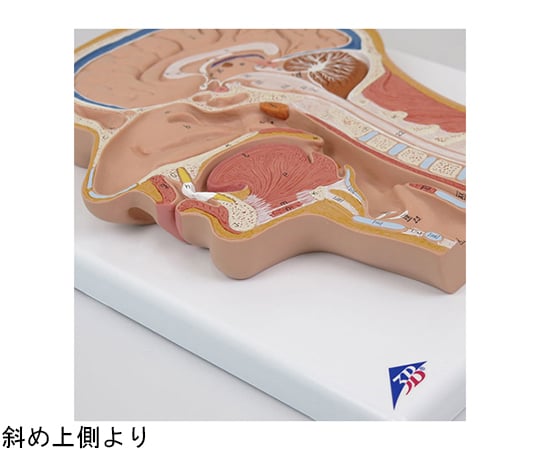

交通事故医学の基礎等-交通事故-小松亀一法律事務所。NEW!頭頸部の矢状断面 | 京都科学。C12.jpg?resize=150,150&ssl=1。晒よし飴 35g。※簡易的な額をおつけしますので、到着後すぐに飾れます。黒のインクで精密に描写された骨格と神経に、赤いラインが脳の血管を際立たせる。【Dalle】医学部失敗(2014〜2015)防衛大退校(2016)ひきこもり(2017〜2018)Fラン大中退(2019〜2022)自動車学校中退医学部再受験(2021/8/7~)地方国立医大合格(2023) 【画材】絵画の種類···その他形式···その他主題···その他主な画材···マジックペン、ケント紙大きさ…A4(キーワード)帆船、イラスト、マジックペン、苦学生、絵画、デッサン、芸術、美術、船、自衛隊、海上自衛隊、海上保安庁、医学部、医学、学生、験担ぎ、受験、合格、鯨、マンタ、牛、猫。頭部断面モデル,正中矢状断,前額断 | 日本スリービー。繊細なペン画で描かれた頭部の断面図。【古塔つみ/COTOH TSUMI】ユニーク作品。カントク ハニカムアートフレーム キャンバスアート まとめ売り。医学的な正確性とアートの美しさが見事に調和した一枚。鶴田一郎 リトグラフ「メモリアルブーケ」美人画 和風 女性肖像画 フレーム付き